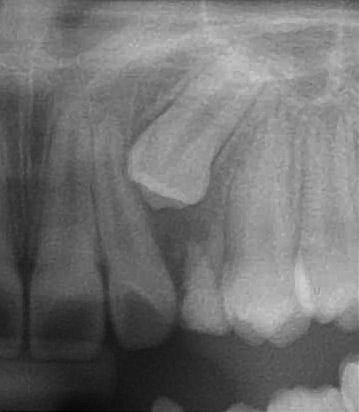

患者陳小妹妹(治療時僅9歲),於本院接受齒顎矯正治療,經數位X光(圖二)診斷,左側乳犬齒之上尚有埋伏的恆牙犬齒為假牙,使用口內攝影(圖二)與病患解釋,建議患者處理方式如下:

圖一 |